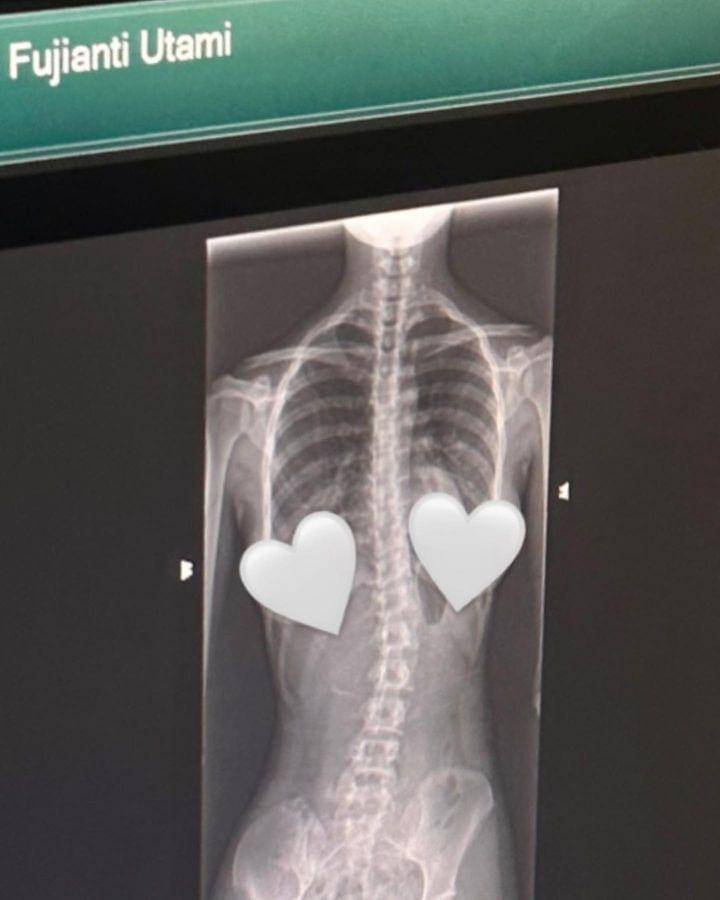

Lewat unggahan tersebut juga, mantan kekasih Thariq Halilintar ini memperlihatkan hasil rontgen. Dalam foto tersebut sangat jelas terlihat, bahwa tulang belakang Fuji agak miring.

"Namanya juga hidup, kadang lurus, kadang miring hehe," tulisnya di caption unggahan tersebut.